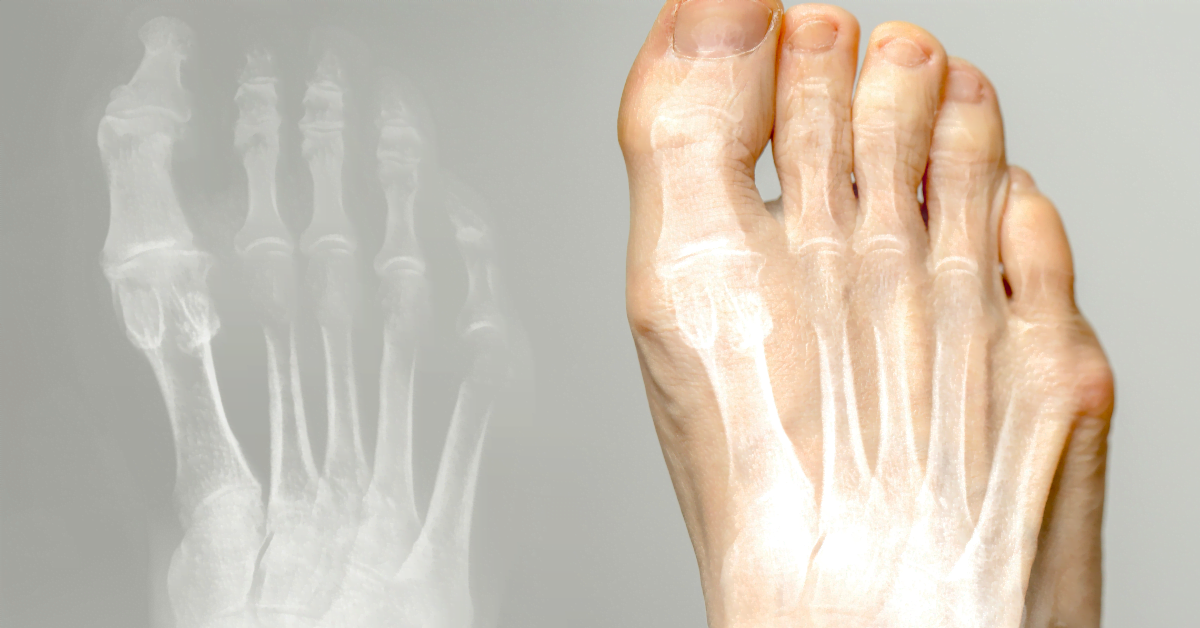

L'alluce valgo (alluce a martello) è una condizione in cui l'alluce è rivolto verso l'interno e forma una protuberanza alla base. Può causare dolore e fastidio. Qui puoi leggere cause, trattamento e prevenzione.

L'alluce valgo è una deviazione dell'alluce verso l'interno, con una protuberanza alla base. Spesso causato da scarpe strette, tacchi alti o fattori ereditari. Può causare dolore e borsite.